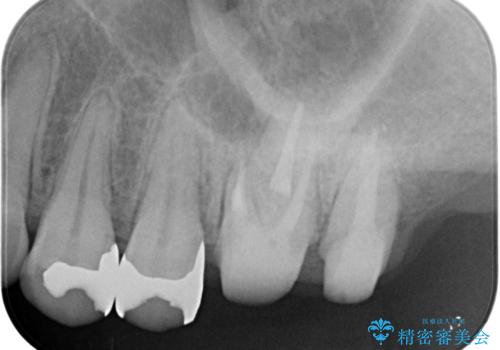

- 銀歯をやりかえたいが他院で抜歯と言われセカンドオピニオンで来院。適合の悪い被せ物が入っており、まずは古い材料、虫歯をとり保存可能か確かめる必要があり、拡大鏡下で全て取り除いたら歯質が歯茎の中まで虫歯がありました。このまま無理やり型取りをして被せ物を作っても不適合な被せ物が入る可能性が高いため歯茎を切り取る手術(ディスタルウェッジ)を行いました。そして再根管治療を行いゴールドの被せ物で治療を行いました。

- PGAクラウン・仮歯 13.2万円×2 精密根管治療(リトリートメント)・コア 16.5万円×2 ディスタルウェッジ 1万円費用は治療当時の料金となります